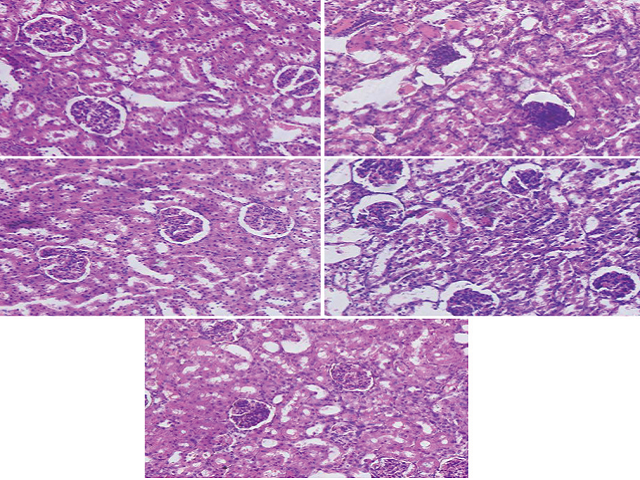

Background: Grape seed proanthocyanidin extract (GSPE) shows a protective effect against cisplatin (cis-dichlorodiammine-platinum (II) [CDDP])-induced nephrotoxicity, but the protection mechanism is still not clear. Objectives: Herein, protective effects of GSPE on cisplatin (CDDP) relevant to oxidative Damage and apoptosis were investigated in rats. Materials and Methods: Randomly divide the experimental animals into five groups: Respectively are normal control group, CDDP model group, GSPE (400 mg/kg) group, CDDP + GSPE (200 mg/kg) group, and CDDP + GSPE (400 mg/kg) group. Each group was administered with distilled water or the corresponding doses of GSPE via gavage for 15 consecutive days. Subsequently, a single intraperitoneal injection of CDDP (8 mg/kg) was administered to the CDDP and CDDP + GSPE groups, and the remaining groups were administered with normal saline via intraperitoneal injection. Results: Based on the histopathological analysis, cisplatin caused structural and functional renal impairment and elevated the levels of serum creatinine and blood urea nitrogen, respectively. Renal injury was caused due to increased lipid peroxidation (LPO)/oxidative stress as evidenced by the increased levels of malondialdehyde and decreased levels of antioxidants including reduced superoxide dismutase, glutathione peroxidase and glutathione. Cisplatin administration also observably increased the rate of apoptosis of renal cortical cells, decreased the expression of Bcl-2, and increased the expression of Bax and caspase-3. The pretreatment of GSPE significantly improved renal function and attenuated the cisplatin-induced LPO/oxidative stress and apoptosis. Conclusion: Our results suggest that that GSPE had a good protective effect against CDDP-induced renal oxidative stress and apoptosis in rats. In addition, the co-administration of GSPE might prove to be a novel and promising preventive strategy against cisplatin-induced nephrotoxicity.